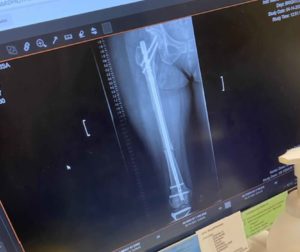

When she called me, of all her injuries, it was the broken left arm that was the most painful. Fracturing the wrist and elbow, she explained that she had Complex Regional Pain Syndrome, and described it like a sunburn, with acid being put on it. Fortunately, she had already recovered from 13 years of chronic pain with Block Therapy and knew how to breathe. She shared that this was her saving grace during the month in the hospital.

The prognosis wasn’t good. They suspected she wouldn’t walk again and never be able to have normal function with her left hand. Here are some photos showing the extent of her fractures at the time of injury.